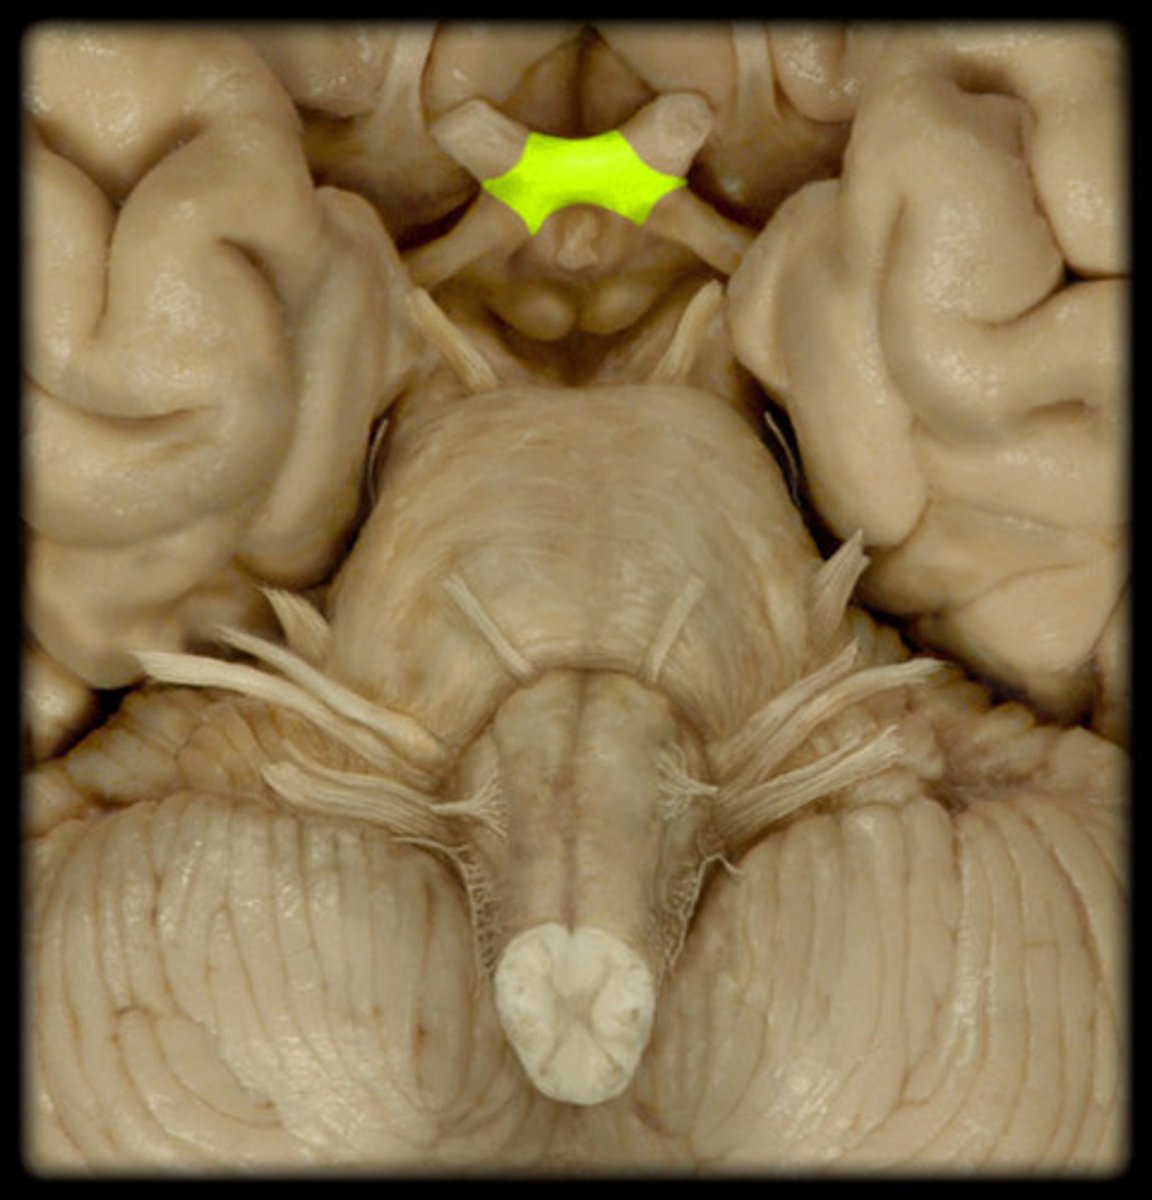

trochlear nerve (CN IV)

Motor cranial nerve that controls movement of the eye inferiorly and laterally; innervates superior oblique muscle

midbrain (mesencephalon)

a small part of the brainstem above the pons that integrates sensory information and relays it upward